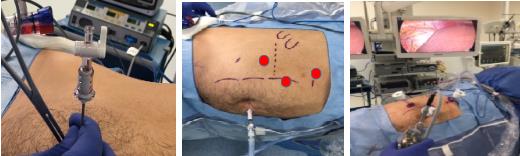

Inserción de trócares para abordaje transperitoneal

No existen normas rígidas para esto, sino más bien, depende de las preferencias y experiencia del cirujano. En nuestro caso, insertamos un primer trocar de 10-12 mm para rectal, a nivel de la 12° costilla, con el objetivo que quede situado al mismo nivel en el cual se encuentra el polo inferior del riñón. A través de este trócar introducimos una óptica de 30° (2,6).

Con la ayuda de la transiluminación proporcionada por la fibra óptica, realizamos la instalación de dos trócares de trabajo de 10-12 mm, separados al menos por 8-10 cm y paralelos al reborde costal, formando un triángulo con el trocar de la cámara. Los trócares accesorios pueden variar en su diámetro dependiendo del uso que se les quiera dar. Por ejemplo, nosotros utilizamos un trocar de 5 mm para una pinza accesoria de 5 mm y uno de 10-12 mm para el separador articulado (Figuras 10 y 11).